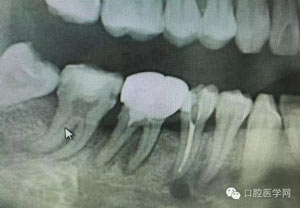

23.jpg

病例1:患者迫切希望保留自己的這一顆牙齒,根尖周陰影比較大,二度松動.而且旁邊有種植修復體,和患者溝通好后,治療好后觀察一個月后冠修復,因為有種植的后期修復,所以有了機會觀察,術后三個月和術后四個月,根尖恢復的還算不錯,希望能夠繼續觀察下去.這樣子的病例,做的時候我們一定要非常的小心,和患者要有充分的溝通以及不同科室的溝通然后決定怎么樣做比較好,假如就是出現了問題,到時候我們也比較好處理些,免得我們自己到時候不好收場。